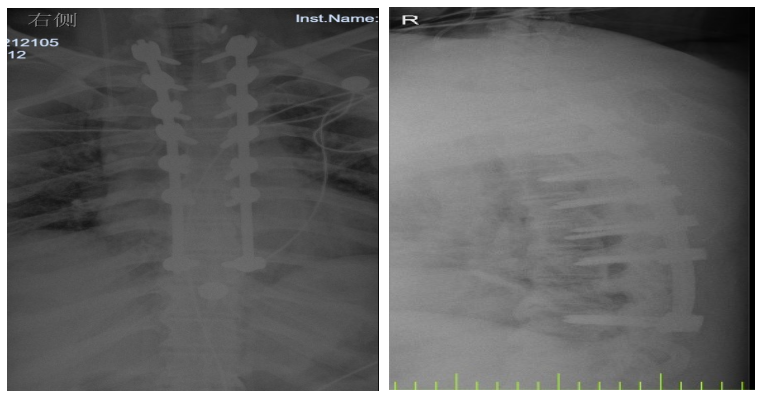

入院后,國文醫(yī)院骨科迅速組織多名專家會診,并為吳先生完善了頸椎及胸椎的 MRI 檢查。結(jié)果顯示,吳先生的頸椎及胸椎多階段嚴(yán)重椎管狹窄,脊髓壓迫超過 50%,情況十分危急。經(jīng)過骨科專家團(tuán)隊(duì)的綜合會診及評估,最終為他制定了一套個性化的治療方案,包括頸椎后路單開門椎管減壓頸椎融合內(nèi)固定術(shù),以及胸椎間盤切除伴椎管減壓胸椎植骨融合內(nèi)固定術(shù)。在完善術(shù)前檢查、確認(rèn)無手術(shù)禁忌后,骨科主任呂國福如期為吳先生實(shí)施了手術(shù)。

手術(shù)涉及頸椎及胸椎多個階段,操作難度極大。專家團(tuán)隊(duì)采用 “蠶食法” 減壓,分塊去除增生韌帶,最大程度減少對脊髓的損傷;同時運(yùn)用椎弓根螺釘固定技術(shù),確保手術(shù)部位的穩(wěn)定性。

術(shù)后 3 天,吳先生的下肢肌力就從 3 級恢復(fù)到了 4 級;術(shù)后 1 個月,胸部束縛感明顯緩解;術(shù)后 3 個月,他已經(jīng)能夠重返工作崗位,生活基本恢復(fù)正常。